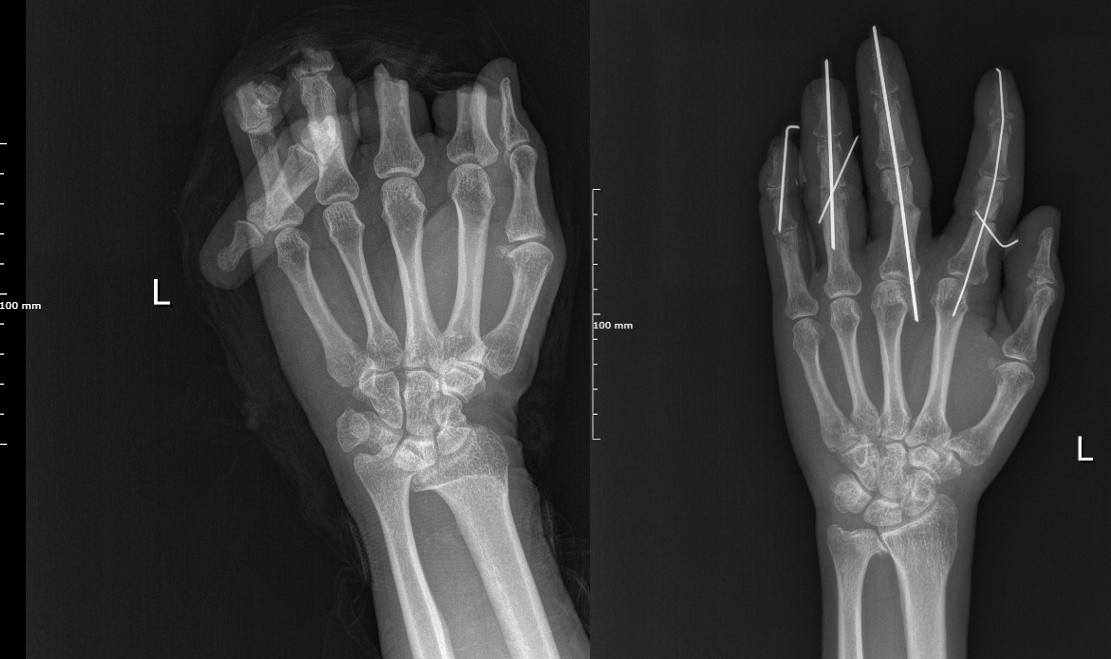

新钢中心医院的急诊室里,47岁的刘先生脸色惨白,声音因恐惧和疼痛而颤抖。他的左手除大拇指外的其他4根手指因机器意外伤害全部离断,瞬间的剧痛过后,是触目惊心的画面:伤口血流如注,组织参差不齐,污染严重,甚至能看见森白的指骨裸露在外。

第二步:骨骼固定。他将裸露的指骨精确对位,用比牙签还细的微型钢针进行内固定,为断指重建坚实的骨架。

第四步:决战时刻——血管神经吻合。这是手术的灵魂,也是决定成败的关键!赵学辉团队凝神静气,手持如发丝般纤细的缝合针线,在显微镜下开始了一场极致的微雕。

医生的双手稳如泰山,眼神锐利如鹰。寻找、对接、缝合……每一个动作都精准到微米级。汗珠从额角渗出,长时间的固定姿势让他们的颈肩无比酸麻,但他们浑然不觉。他们的全部精神,都凝聚在那一方小小的视野里,在那根关乎手指生死的血管上。

整整6个小时,360分钟的极致专注,赵学辉和他的团队,用高超的技艺和非凡的毅力,终于打赢了这场“手指保卫战”,将断裂的血管、神经、骨骼和肌腱一一重新连接。